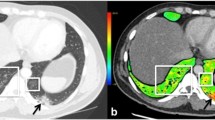

DECT angiography identified overt PE in only two patients (6.5%). In the lung perfusion maps, these patients had PDs corresponding to the areas with vascular occlusion and areas of decreased perfusion without visible thrombus (Fig. 1). Apart from these two cases, PDs were visualized in six more patients who had no detectable emboli in the pulmonary arteries (Fig. 2). In total, there were 8 patients with PDs and 2 patients among them had gross filling defects in the pulmonary arteries. The PDs did not overlap with GGOs or consolidation. In the subgroup analysis, patients with PDs had prolonged hospital stays (12.28 ± 8.81 vs 6.83 ± 5.04 days, p = 0.138), higher rates of ICU admission (37.5% vs 4.3%, p = 0.043), higher CT scores (13.3 ± 8.2 vs 5 ± 5.4, p = 0.025), and a more severe (type 3) disease (50% vs 4.3%, p = 0.010). The only significantly frequent clinical symptom in the patients with PDs was sore throat (50% versus 13%, p = 0.031). BMI was higher in patients with PDs (28.85 ± 3.77 vs 25.94 ± 3.12 kg/m2, p = 0.040). Smoking status was similar in the two groups (25% vs 26%, p = 0.952) (Table 1). Ferritin, AST, fibrinogen, D-dimer, CRP, and troponin plasma levels were significantly higher, and albumin levels were significantly lower in patients with PDs (Table 2). A receiver operator characteristic (ROC) curve analysis revealed that D-dimer plasma levels ≥ 0.485 μg/L predicted lung PD with 100% specificity and 87% sensitivity (area under the (AU)ROC, 0.957) and with a positive predictive value of 80% and a negative predictive value of 100% (Fig. 3). When we grouped patients according to the extent of PDs, there were statistically significant differences in terms of clinical classification, CT score, presenting symptoms like sore throat, and the need for oxygen therapy (Table 3). D-dimer was the only laboratory variable related to PD (p = 0.01).

A 47-year-old male with coronavirus disease 2019 (COVID 19). Pulmonary thromboembolism (PE) can be seen in the right lobar and segmental pulmonary arteries (arrows) on pulmonary dual-energy computed tomography (DECT) angiography images (a and b). On the perfusion map images (c), perfusion deficits due to the PE (arrows) can be seen in the right lung. There are also perfusion deficits in the left lobe, which are not associated with vessel occlusion or parenchymal findings (arrowheads). On coronal renal perfusion images (d), heterogeneous kidney enhancement (arrows), and a PE in the right lower lobe pulmonary artery (large arrow) can be seen